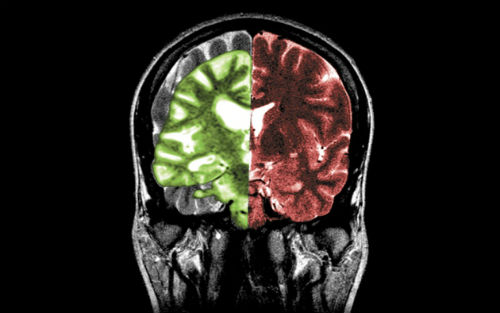

研究人员在大脑灰质和血管中都发现了由β-淀粉样蛋白沉淀形成的斑块。对照组试验以年龄类似、没有接受过硬脑膜移植手术但是死于CJD疾病的患者大脑为样本,研究人员并没有发现类似的淀粉样蛋白累积。这可能意味着,硬脑膜移植手术除了引发朊蛋白传染之外,还可能导致β-淀粉样蛋白的传染。